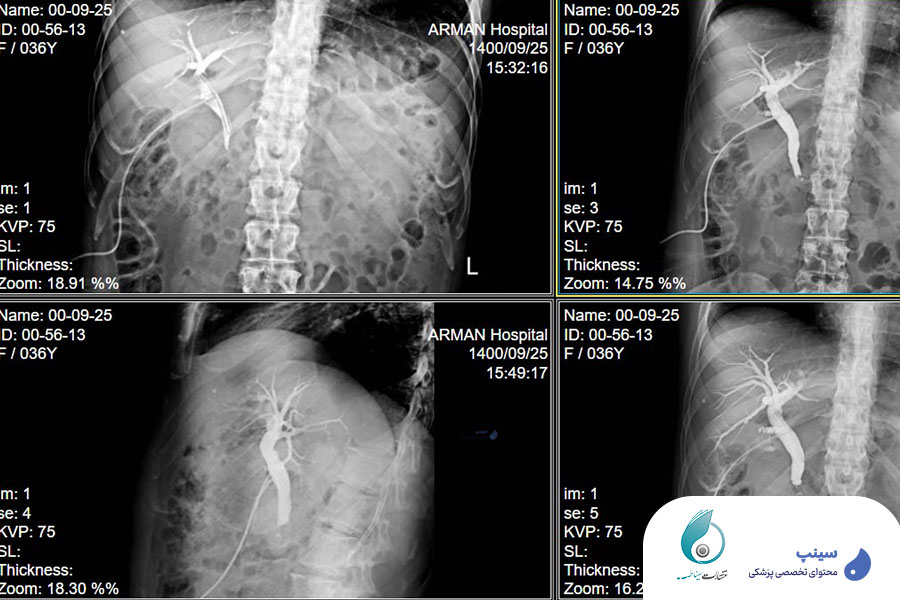

در این دوره، سعی شده تا تعداد زیادی از کیس های واقعی بررسی شود. تصاویر رادیولوژیک آنها یک به یک برای شما ارائه میشود تا بتوانید مباحث را به صورت کاملا عملی فرا بگیرید و نحوه تحلیل و آنالیز هر یک را بیاموزید. ارائه درس به همراه تصاویر کیس های واقعی، نه تنها باعث مرور مباحث تئوری و علمی این حوزه خواهد شد، بلکه سبب افزایش تسلط شرکت کنندگان در مهارت های عملی نیز خواهد گردید.

در این دوره تلاش شده است تا آموزش بر اساس کیس های واقعی طراحی شود و تمامی مباحث در قابل تصاویر و نتایج عملی از بیماران ارائه گردد. همین امر در آینده به شما کمک میکند تا در صورت مشاهده تصاویر مشابه، تشخیص دقیق تر و سریع تری داشته باشید. این رویکرد باعث میشود که شما بتوانید در شرایط بالینی هم دقت و سرعت تشخیص خود را افزایش دهید.